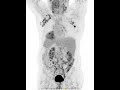

Лучевая терапия ЛТ — один из локальных местных способов лечения онкологических заболеваний, при котором точно подведенные высокие дозы облучения радиации используются для уничтожения опухолевых клеток. Подобное излучение, но в гораздо меньших дозах, применяется при проведении рентгенологических исследований, например, флюорографии, компьютерной томографии КТ и так далее. Для проведения ЛТ применяются рентгеновские лучи, гамма-лучи и заряженные частицы. Принцип действия ЛТ основан на её повреждающем действии на цепочки ДНК, за счет прямого разрушения связей между основаниями ДНК или образования заряженных частиц свободных радикалов. Следствием этого является то, что ЛТ не способна уничтожить опухолевые клетки мгновенно, их гибель происходит постепенно, в течение дней или недель после проведения облучения. Облучение повреждает не только опухолевые, но и нормальные клетки, что является причиной развития нежелательных явлений и осложнений проведения ЛТ подробнее — ниже. Врач-радиолог обязательно учитывает данный факт при планировании лечения, стараясь максимально защитить нормальные ткани за счет точного подведения пучка облучения, а также ограничения дозы облучения — максимальная переносимая доза радиации для здоровых тканей выше, чем для опухоли.